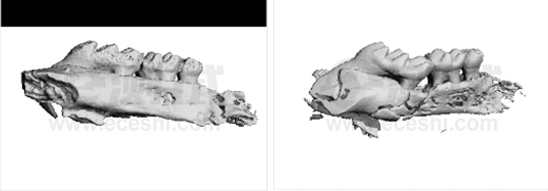

2.小鼠牙齒三維重建

b5bfcb8e5bc50f2ed9f2bc9dabc13643